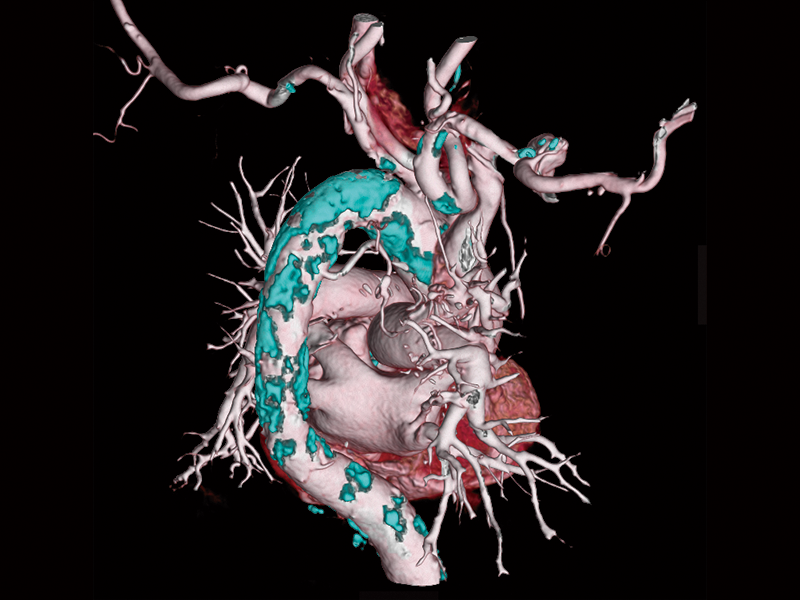

Interstitial pneumonia

Lung screening (CTDlvol: 2.0 mGy)

Coronary artery calcifification

Non-tuberculous mycobacteria

Follow-up after CABG

Follow-up after LAD stenting